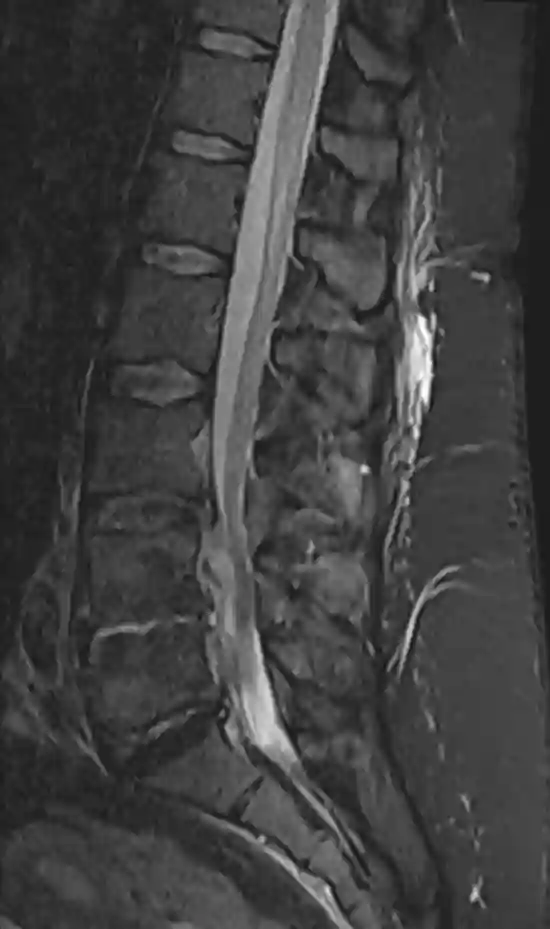

MRI STIR Fraktur

Sagittale MRI STIR Sequenz eines Patienten mit einem frisch frakturiertem Wirbelkörper.